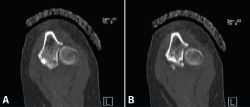

Figura 4. Cortes axiales de tomografía computarizada a los 10 días de la lesión. A: fractura de la punta de la coronoides que se extiende hacia la base de la coronoides; B: fractura conminuta al nivel de la faceta anteromedial de la coronoides.